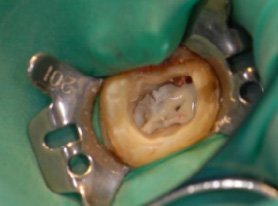

この方のお口の中の状態が、左上の写真です。このような金属の被せ物をご使用中の方もいらっしゃるかと思います。

これらの銀歯と土台を除去してみると、内部が黒く変色していることが確認できました。変色部分と金属の被せ物を丁寧に除去し、金属を使用しない被せ物に置き換えました。